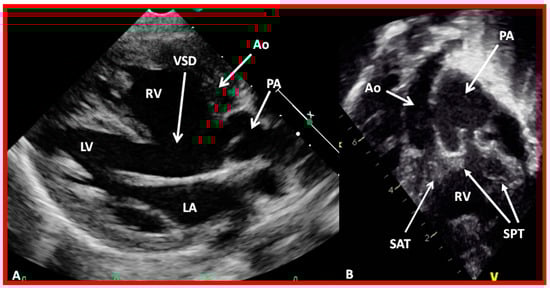

Figure 48. Echo frames from the parasternal long axis (A) and subcostal (B) views illustrating that both the aorta (Ao) and the pulmonary artery (PA) arise from the right ventricle (RV), i.e., double-outlet right ventricle. Note that the great vessels are normally related to each other. A ventricular septal defect (VSD) (vertical arrow) is also seen. The conal tissue (CT) is shown by thin arrows in (B). The vessel marked PA was traced further and demonstrated to subdivide into right and left pulmonary arteries. Left atrium (LA) and left ventricle (LV) are labeled. Modified from reference [43].

Figure 49. Echo images from the parasternal long axis (A) and subcostal (B) projections of a child with Taussig-Bing type of double-outlet right ventricle (with transposition of great vessels) illustrating that both the pulmonary artery (PA) and the aorta (Ao) arise from the right ventricle (RV). A large ventricular septal defect (VSD) and subaortic (SAT) and subpulmonary (SPT) tissues are also shown. The vessel marked PA was further traced and was demonstrated to divide into right and left PAs. Left atrium (LA) and left ventricle (LV) are labeled. Modified from reference [43].